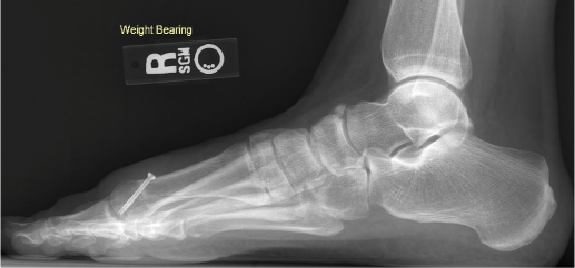

Either way, the multiple classification systems available should not be utilized alone to determine surgical treatment. More often I find that these systems ignore instability, elevation, or metatarsal length. As some studies concluded, classification failed to correlate with every patient.7,8 Roukis and colleagues in 2002 presented his four-stage radiographic analysis—which finally incorporated some radiographic measurements to include metatarsal protrusion, intermetatarsal angle, and talo-first metatarsal angles—which looks at elevatus, as shown in Figure 2 above and Figure 3 below.9 He then followed that up with an article on metatarsus primus elevatus in 2005.10 Then Elliott and colleagues’ 2016 follow-up review11 on Roukis’s 2002 study9 concluded that regardless of the etiology or surgery performed, patients were happier; however, their ROM never improved.

long history of plantar fasciitis. B. The below X-ray shows elevation, with the first metatarsal head not even touching the floor.